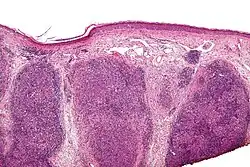

| Low magnification micrograph of a lymphoepithelioma-like carcinoma showing the characteristic squamoid nests in association with clusters of lymphocytes. H&E stain. | |